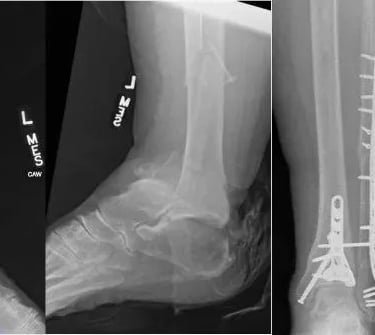

Foot and ankle conditions

Complex Trauma Care

Specialized treatment for severe fractures and injuries to restore function and mobility.